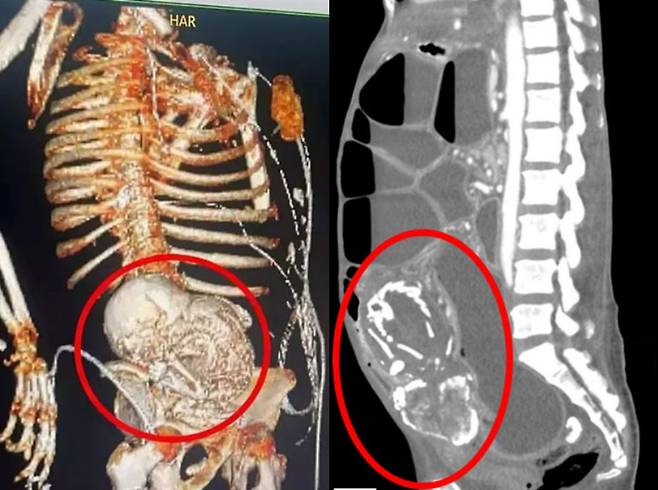

최근 외신 매체 데일리메일에 따르면, BBC 드라마 ‘콜 더 미드와이프’에서 ‘리토페디온’이라 불리는 매우 희귀한 임신 현상을 조명하는 이야기가 방영됐다. 리토페디온(석태아)은 자궁이 아닌 복강에서 착상한 태아가 사망해 산모의 면역 반응으로 석회화돼 돌처럼 굳는 극히 드문 현상이다. 1970년대를 배경으로 하는 이 드라마는 실제로 300건가량 보고된 실존 의학 현상을 바탕으로 제작됐다.

리토페디온은 자궁이 아닌 복강에서 수정란이 착상하는 복강 내 임신의 결과로 발생한다. 태아가 여성의 난소나 자궁 이외의 복부 내에서 자라다 사망하면 산모의 면역 체계가 이를 이물질로 인식해 감염을 막기 위한 방어 반응을 일으킨다. 이때 석회질이 태아를 둘러싸며 침착되고, 시간이 지나면서 단단하게 굳어 석태아가 된다.

대부분 복통이나 장기 압박 증상을 동반하지만, 수십 년 동안 아무런 증상 없이 지내는 경우도 많다. 일부는 사망 후 부검에서야 발견되기도 한다. 전문가들은 “현대 의학에서는 초음파와 혈액검사를 통해 자궁 외 임신을 조기에 진단할 수 있어 과거보다 발생 가능성이 매우 낮다”며 “임신 후에는 정기 검진을 받는 게 중요하다”고 전했다.